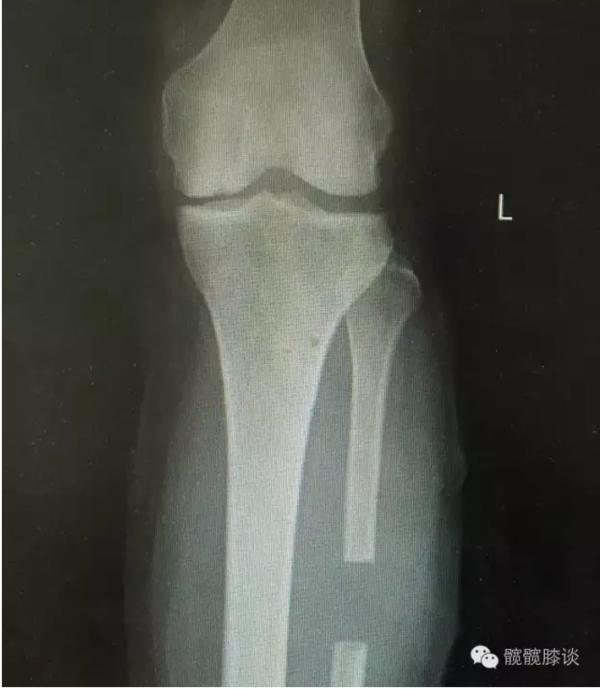

膝关节不均匀沉降术后患者X线片(下图)

术前片:

术后图如下: